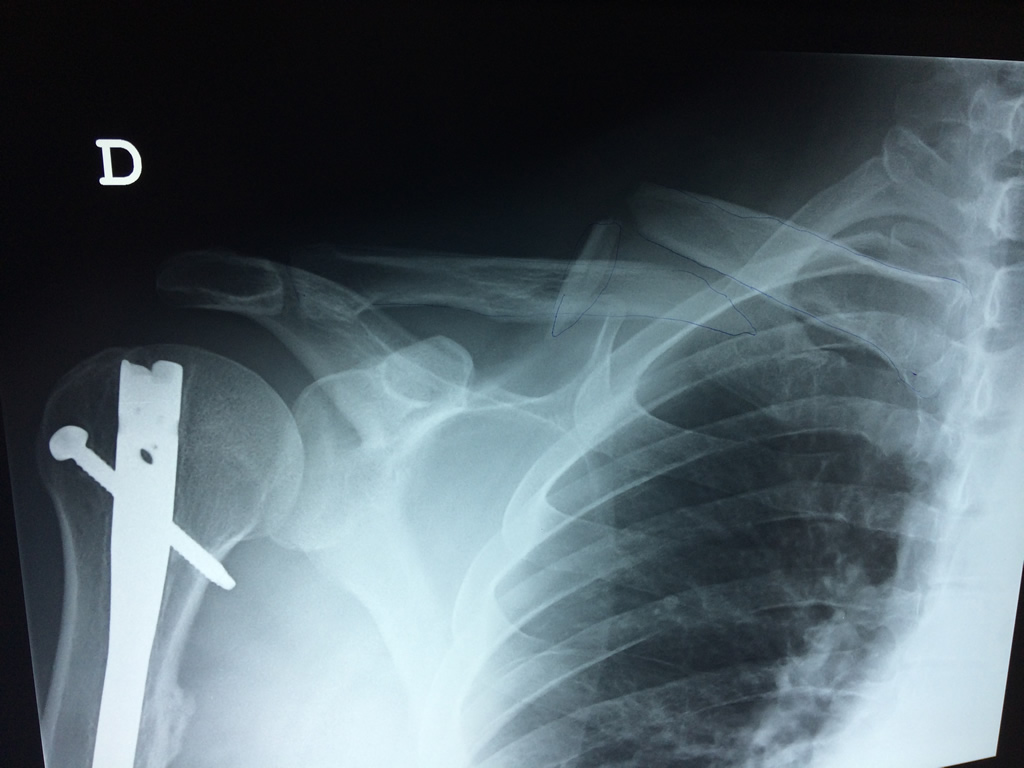

Cirugía de Fémur - Clavícula